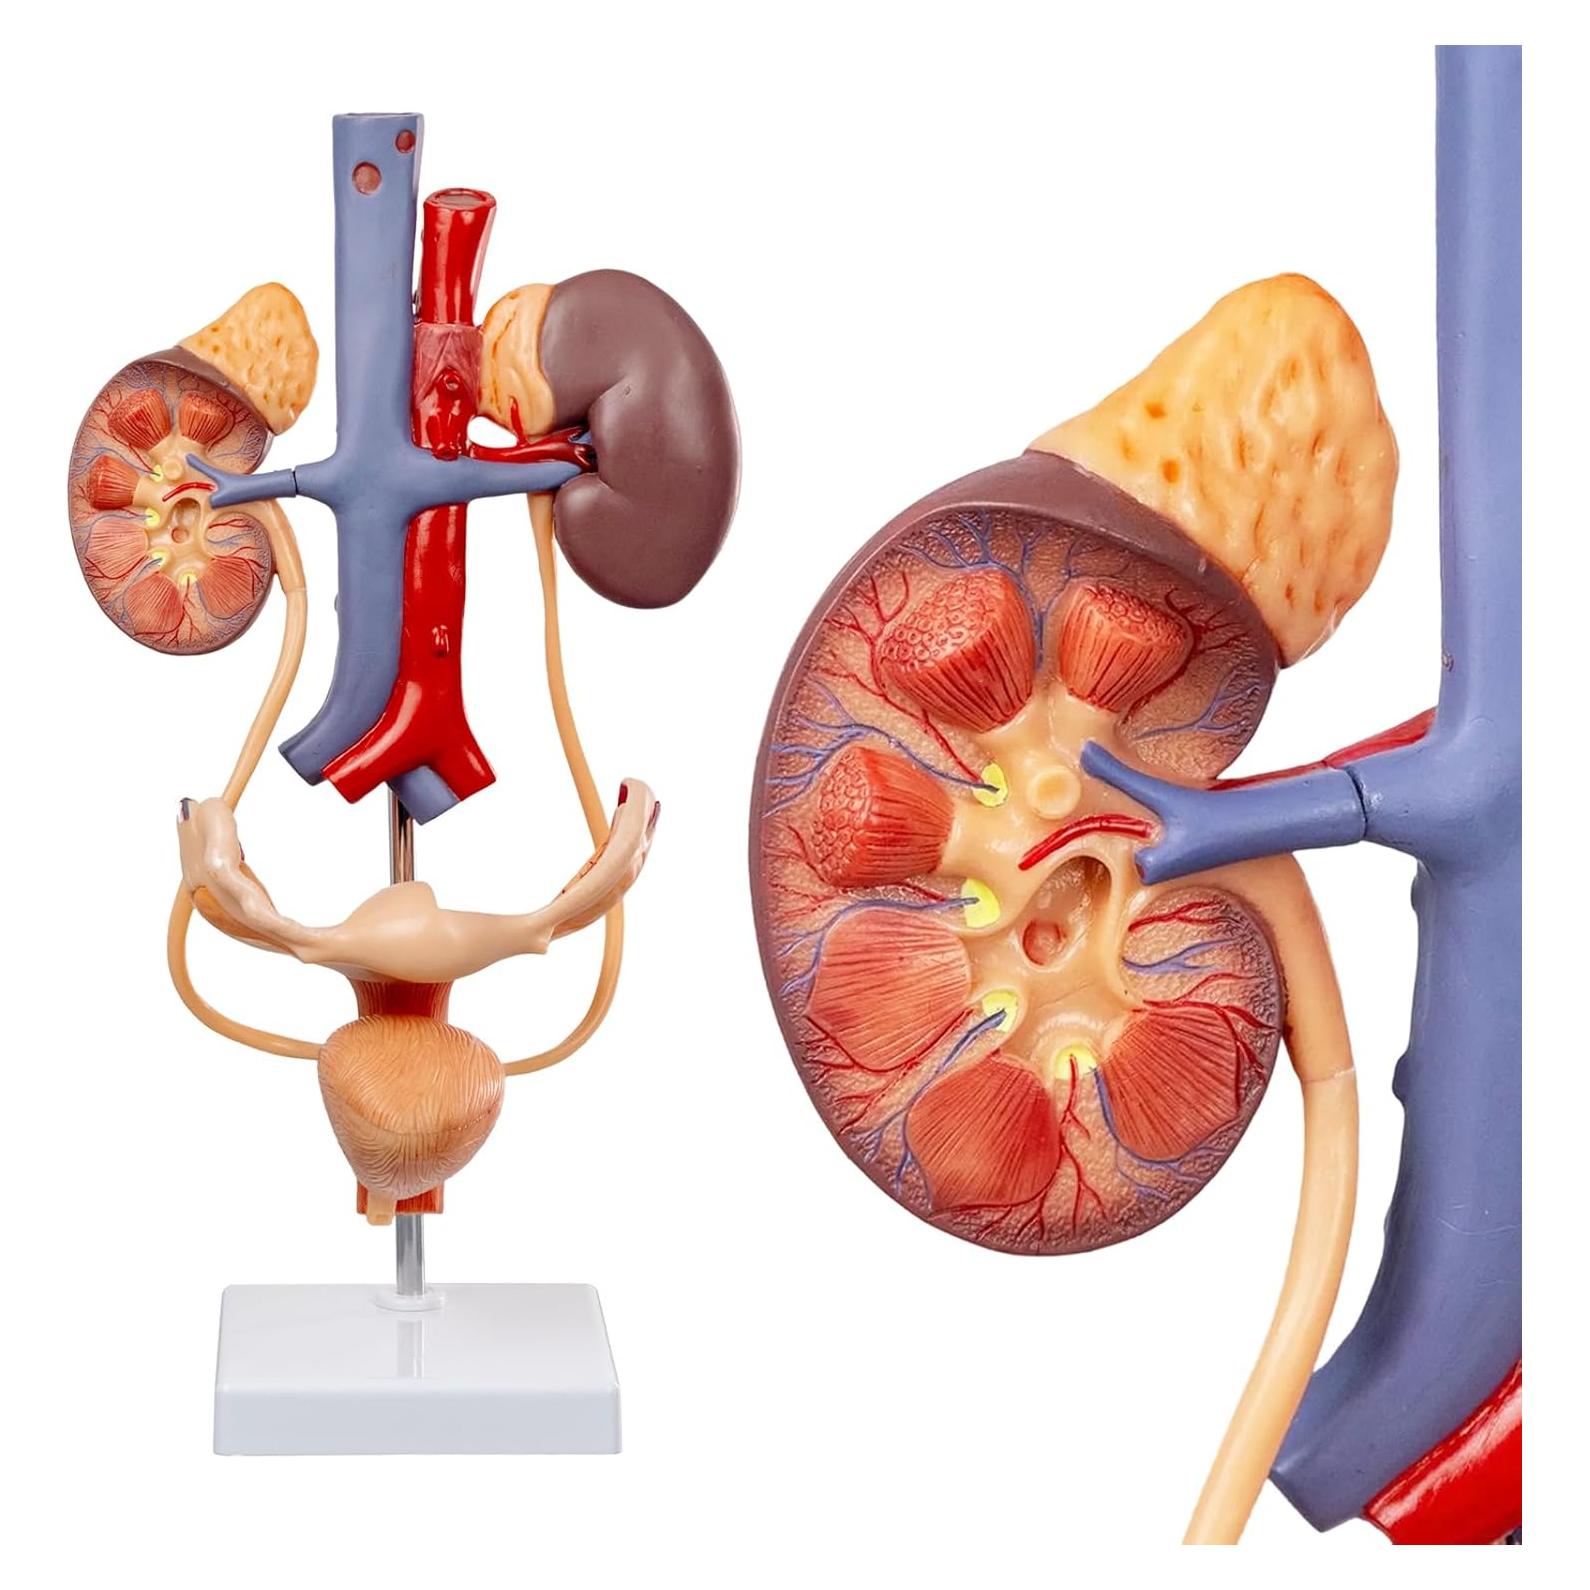

Modelos Anatómicos de Órganos marca Evotech (20 productos)

Modelos Anatómicos 3D EVOTECH SCIENTIFIC - Cuerpo, Corazón y Esqueleto